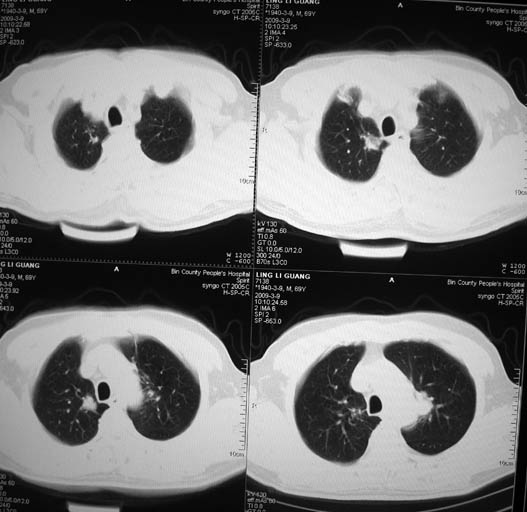

以下是引用随光逐影在2009-3-9 21:36:00的发言:[br]1)两肺上叶尖段结节状病灶,性质待定(不排除肿瘤可能);建议追踪复查。2)右肺中叶内侧段炎症。